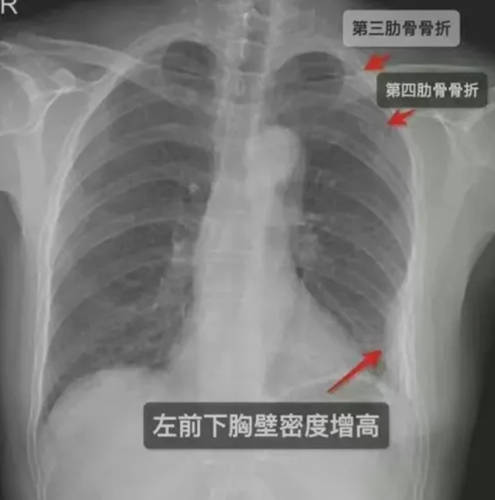

بعد 5 أيام من العناق الشديد، اشتد الألم فى صدر المرأة، فذهبت أخيرا إلى المستشفى لإجراء فحص طبى، كشف فحص بالأشعة السينية أنها لم يكن لديها ضلع واحد بل 3 مكسورين، اثنان على الجانب الأيمن من قفصها الصدرى وواحد على اليسار، فاضطرت إلى أخذ إجازة من العمل، ما أدى إلى فقدان الدخل، كما أنفقت مبالغ كبيرة على الفواتير الطبية وخدمات التمريض.

وأمر القاضى مؤخرا الرجل بدفع 10 آلاف يوان ما يعادل 1500 دولار أمريكى، لزميلته كتعويض عن كسر ضلوعها عن طريق العناق، على الرغم من اكتشاف الأضرار التي لحقت بالأضلاع بعد 5 أيام، قالت المحكمة إنه لا يوجد دليل يثبت أنه خلال تلك الأيام الـ 5 شاركت المرأة فى أى أنشطة يمكن أن تسببت في كسر العظام، بالإضافة إلى ذلك، كانت هناك شهادات من زملاء العمل الذين تذكروا رد فعل المرأة المؤلم بعد العناق.